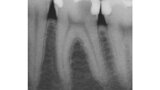

Aplikace MTA s použitím Produit Dentaires (PD) MAP System